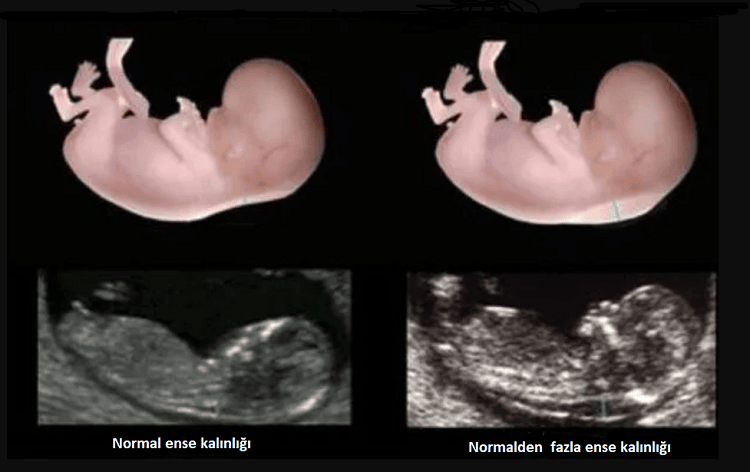

Ense saydamlığı veya NT (nuchal translucency) olarak da isimlendirilen ense kalınlığı, gebeliğin ilk üç ayında fetal boynun arkasındaki deri altında sıvı toplanmasının sonografik görünümüdür. Kromozom anormallikleri, kalp kusurları ve birçok genetik sendromlu fetüslerde NT kalınlığı artar.

Ense kalınlığı bebekte Down sendromu belirtilerinden biridir ve risk düzeyi ölçümünde kullanılır. Anne kanından bakılan beta-HCG ve PAPP-A ölçümü ile birlikte yapılan ense kalınlığı ölçümü gebeliğin ilk üç ayında bakılan ikili testi oluşturmaktadır. Bu test Down sendromu riskinin belirlemede %80-85 oranında hassas bir testtir.

NT Sınır Değerleri

Gebelik haftası ilerleyip anne karnındaki bebek büyüdükçe NT kalınlığı da artar. Kalınlığın gebelik haftasına göre 95 persentil ve üzerinde olması durumunda normalden fazla kalın olarak değerlendirilir. 11-14. haftalar arasında genellikle 3 mm’nin üstü artmış olarak değerlendirilmektedir.